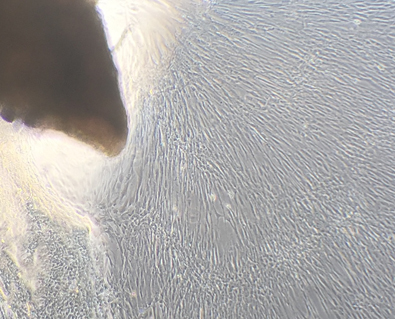

My skin cells (fibroblasts) growing in a petri dish (in vitro) from a piece of skin tissue taken from my arm.

It’s hard not to invest the whole of biology with intentions, purposes, wants and needs, even though cells and simple organisms resemble automata responding without volition to the signals from their environment. (Some would say this applies to humans too.) That’s just how nature works.

Yet seeing these cells do their business in a petri dish is to recognize that life exists in doing. It is a process in which change is the only constant: change imbued with direction, more or less constrained onto a trajectory that evolution has guided and given what looks almost indistinguishable from a purpose, until death makes that change an inexorable slide into decay and entropic dissolution. There is no agreed scientific definition of “life”, but such a thing (if it is possible at all) would mean little if it fails to acknowledge this dynamic aspect, this interplay of predetermined pattern and historical contingency. It feels banal to say that my excised cells took on a life of their own, but what is so new and so remarkable about the science behind organoids is that we have the knowledge and power to influence the direction that life takes.